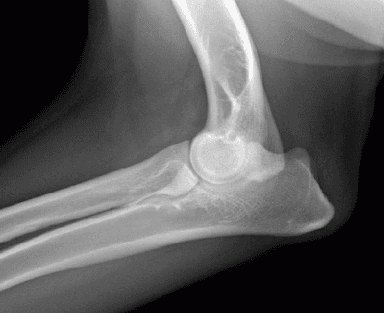

Normal Elbow

The elbow is a complex joint made up of three bones — the radius, ulna, and humerus — which must align and move together precisely. Any incongruity in their fit or growth leads to uneven force distribution, abnormal wear on the cartilage, and progressive joint damage.